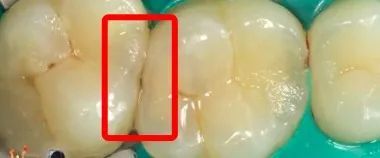

看到这里,大家对于邻面龋“不易发现、发现即晚”的特征有所了解了吧。我们再来看一个磨牙的案例。下图中是磨牙的缝隙,肉眼看上去,好像问题也不大。

图片

可是呢,等医生用工具处理之后,已经是这么大的一个洞了。因为坏的面积大、深度大,甚至已经伤及牙根了,只能做根管治疗了。